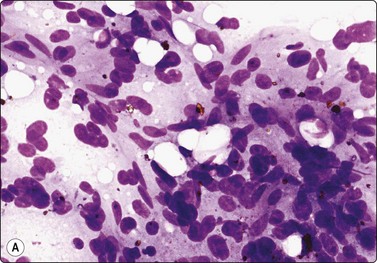

Transitional cell carcinoma (Figs 12.29-12.31)106,107

image

Fig. 12.29 Transitional cell carcinoma of renal pelvis

Loosely clustered malignant epithelial cells; pleomorphic hyperchromatic nuclei; moderate amount of dense cytoplasm; necrotic debris (MGG, HP).

Fig. 12.30 Transitional cell carcinoma of renal pelvis

Poorly cohesive malignant cells with relatively high N:C ratio; pale cytoplasm; vesicular nuclei; prominent nucleoli (Pap, HP).

image image

Fig. 12.31 Transitional cell carcinoma

(A) Mixed population of non-neoplastic tubular epithelium and malignant cells with dense cytoplasm and eccentric nuclei (MGG, HP); (B) Corresponding tissue section; carcinoma cells infiltrating between normal renal structures (H&E, IP).

Criteria for diagnosis

High cellularity; cells single and in syncytial clusters; rarely papillary structures,

Large pleomorphic nuclei; variable hyperchromasia; coarse chromatin,

Eccentric nuclei within a dense cytoplasm,

Prominent nucleoli,

Cercariform cells often present,

Most tumors are CK7+ and CK20+.

Transitional cell carcinoma (TCC) developing from the epithelial lining of the renal pelvis involves the parenchyma by invasion and the malignant cells may therefore be intimately mixed with non-neoplastic tubular epithelial cells in FNB smears (Fig. 12.29). Most of the tumors subjected to FNB are solid and high grade, and true papillary structures are not often found. A tendency to squamous differentiation is not uncommon, some tumors have a spindle cell pattern and some are highly anaplastic and cannot easily be identified as of transitional cell origin. So-called ‘cercariform’ cells, which have long unipolar cytoplasmic processes with a thickening at the tail, are regarded as a clue to the recognition of TCC in smears.108,109

The distinction between RCC and TCC is not always easy. TCC sometimes has a clear cell appearance in tissue sections and correspondingly a pale vacuolated cytoplasm in smears. This is usually a focal phenomenon; the nuclear:cytoplasmic ratio is still relatively high and the nuclei are hyperchromatic with a coarse, irregular chromatin. Tumor cells are positive for CK7, usually also for CK20, high molecular weight cytokeratin and thrombomodulin, negative for RCC antigen and CD10.